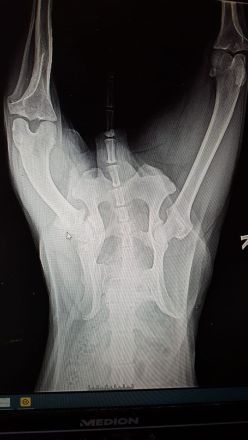

Sein Becken ist deformiert (siehe Foto Röntgenbild), deshalb wurde Benni von seinen Adoptanten zu mir zurück gebracht, sie wohnen im 2. Stock

ohne Fahrstuhl. Benni sollte nämlich keine Treppen steigen. Eine OP würde kaum etwas verbessern. Benni rennt, spielt und macht lange Spaziergänge mit, trotz der "Verletzung".